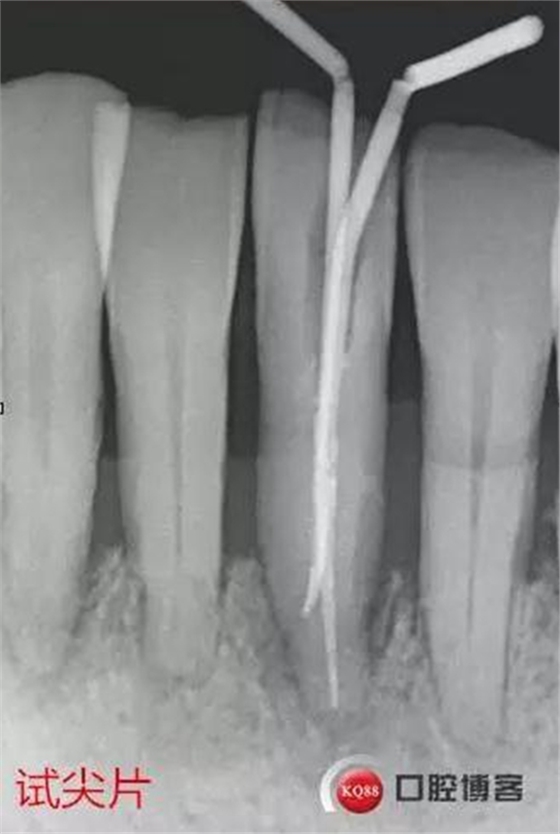

處理:上橡皮障,31開髓,測(cè)工作長(zhǎng)度17mm,含氯沖洗液沖洗,機(jī)擴(kuò)至04錐度30#,超聲蕩洗,一次性根充。33-43牙齒鄰接處super bond粘結(jié)固位,行松牙固定。調(diào)合。拍根充術(shù)后片,未達(dá)根尖,懷疑遺漏根管,去除根充物后,繼續(xù)探查根管,找到舌側(cè)根管,測(cè)長(zhǎng)度20mm,時(shí)間原因,未行擴(kuò)根,氫氧化鈣暫封。

圖省事,沒(méi)有拍術(shù)中試尖片,導(dǎo)致術(shù)后重新去除根充物,再次探查,耽誤時(shí)間。

想當(dāng)然的認(rèn)為31單管,忽略了尚有5-10%概率的雙根管情況。

事后再次查看術(shù)前片,可以看到兩個(gè)根管影像,忽略了。